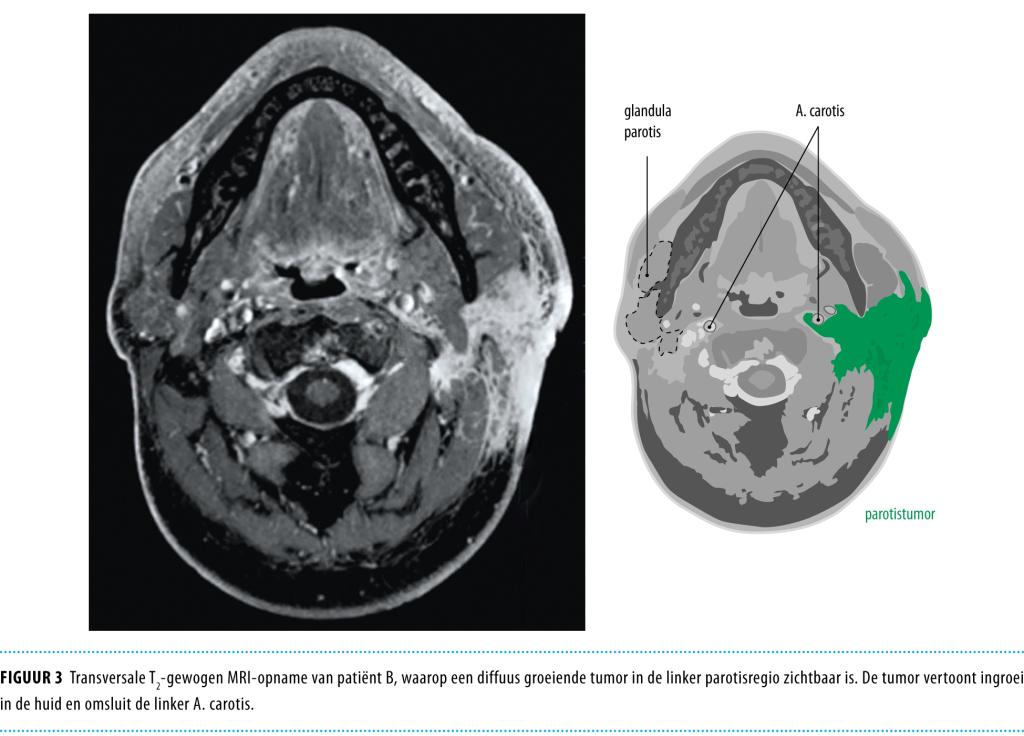

Uit het opgevraagde histopathologische rapport van destijds bleek dat er sprake was geweest van een pleiomorf adenoom, reikend tot in het snijvlak. Er werd een MRI verricht die een grote, diffuus infiltrerende afwijking liet zien, zich uitstrekkend van de uitwendige gehoorgang tot de clavicula; deze afwijking sloot tevens de A. carotis in (figuur 3). Met echografie werd dit inhomogene beeld bevestigd; circumscripte tumorbegrenzingen waren niet in beeld te brengen.

Figuur 3